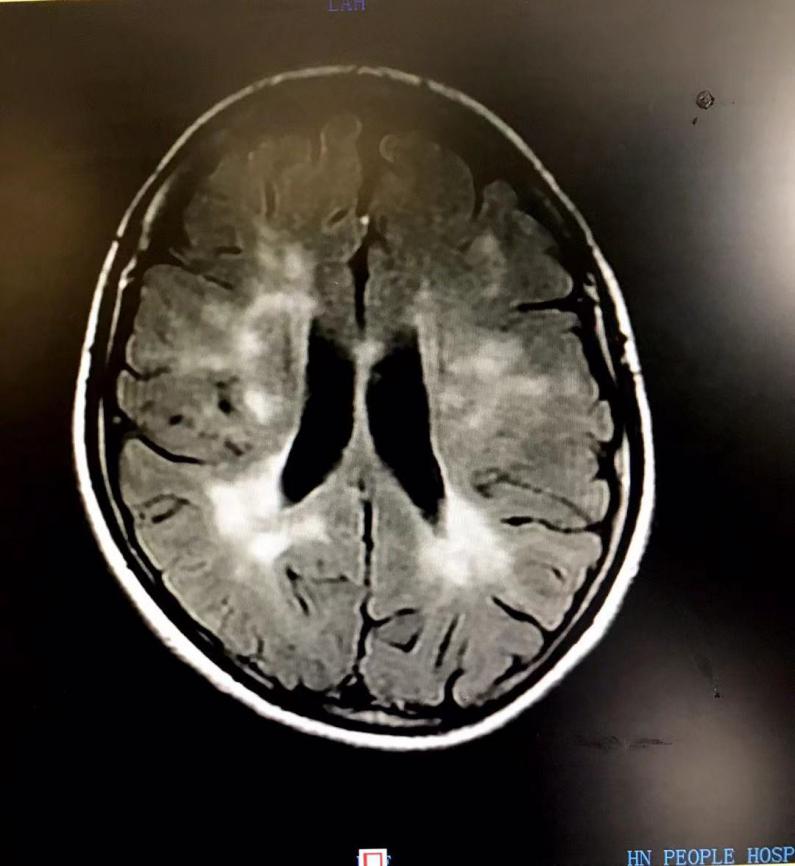

核磁共振检查显示病灶

入院时,王女士右侧肢体乏力已经5天,严重时右侧肢体不能活动,完善相关检查及脑脊液检测,诊断为炎性脱髓鞘病变、多发性硬化。通过药物治疗,结合康复锻炼,王女士已康复并能独立行走,一周后步行出院。